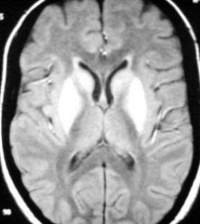

保持病儿呼吸道通畅消除口腔分泌物必要时给氧发生痉挛时立即以针灸治疗或用短效的镇静剂忌用吗啡和其他呼吸抑制剂以及茶碱氨茶碱琥珀酰胆碱利血平新斯的明毒扁豆碱吩噻嗪安定呼吸衰竭者除注射呼吸剂和人工呼吸外必要时作气管插管正压给氧及时处理脑水肿和肺水肿注意保护肝肾功能心脏骤停时速作体外心脏按压并用1∶10000肾上腺素0.1ml/kg静脉注射必要时可在心腔内注射阿托品在静滴解毒剂同时适量输液以补充水分和电解质的丢失但须注意输液的量速度和成分在有肺水肿和脑水肿的征兆时输液更应谨慎严重病例并用肾上腺皮质激素在抢救过程中还须注意营养保暖排尿预防感染等问题必要时适量输入新鲜血液或用换血疗法